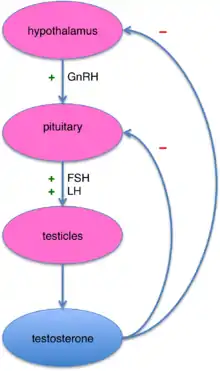

Primary gonad failure

Primary failure of the ovaries or testes (gonads) (hypergonadotropic hypogonadism) will cause delayed puberty due to the lack of hormonal response by the final receptors of the HPG axis.[7] In this scenario, the brain sends a lot of hormonal signals (high gonadotropin), but the gonads are unable to respond to said signals causing hypergonadotropic hypogonadism.[7] Hypergonadotropic hypogonadism can be caused by congenital defects or acquired defects.[39]

Hormonal pathway defects

The hypothalamic–pituitary–gonadal axis can also be affected at the level of the brain.[39] The brain does not send its hormonal signals to the gonads (low gonadotropins) causing the gonads to never be activated in the first place resulting in hypogonadotropic hypogonadism.[41] The HPG axis can be altered in two places, at the hypothalamic or at the pituitary level.[41] CNS disorders such as childhood brain tumors (e.g. craniopharyngioma, prolactinoma, germinoma, glioma) can disrupt the communication between the hypothalamus and the pituitary.[34] Pituitary tumors, especially prolactinomas, can increase the level of dopamine causing an inhibiting effect to the HPG axis.[15] Hypothalamic disorders include Prader-Willi syndrome and Kallmann syndrome,[3] but the most common cause of hypogonadotropic hypogonadism is a functional deficiency in the hormone regulator produced by the hypothalamus, the gonadotropin-releasing hormone or GnRH.[7]

Lab tests

The first step in evaluating children with delayed puberty involves differentiating between the different causes of delayed puberty. Constitutional delay can be evaluated with a thorough history, physical, and bone age.[4] Malnutrition and chronic diseases can be diagnosed through history and disease-specific testing.[3] Screening studies include a complete blood count, an erythrocyte sedimentation rate, and thyroid studies[3]. Hypogonadism can be differentiated between hyper- and hypo-gonadotropic hypogonadism by measuring serum follicle-stimulating hormone (FSH) and luteinizing hormone (LH) (gonadotropins to measure pituitary output), and estradiol in girls (to measure gonadal output).[7][39] By the age of 10-12, children with failure of the ovaries or testes will have high LH and FSH because the brain is attempting to jump-start puberty, but the gonads are not responsive to these signals.[7][3]

Stimulating the body by administering an artificial version of gonadotropin-releasing hormone (GnRH, the hypothalamic hormone) can differentiate between constitutional delay of puberty and a GnRH deficiency in boys, although no studies have been done in girls to prove this.[7][42] It is often sufficient to simply measure the baseline gonadotrophin levels to differentiate between the two.[10]